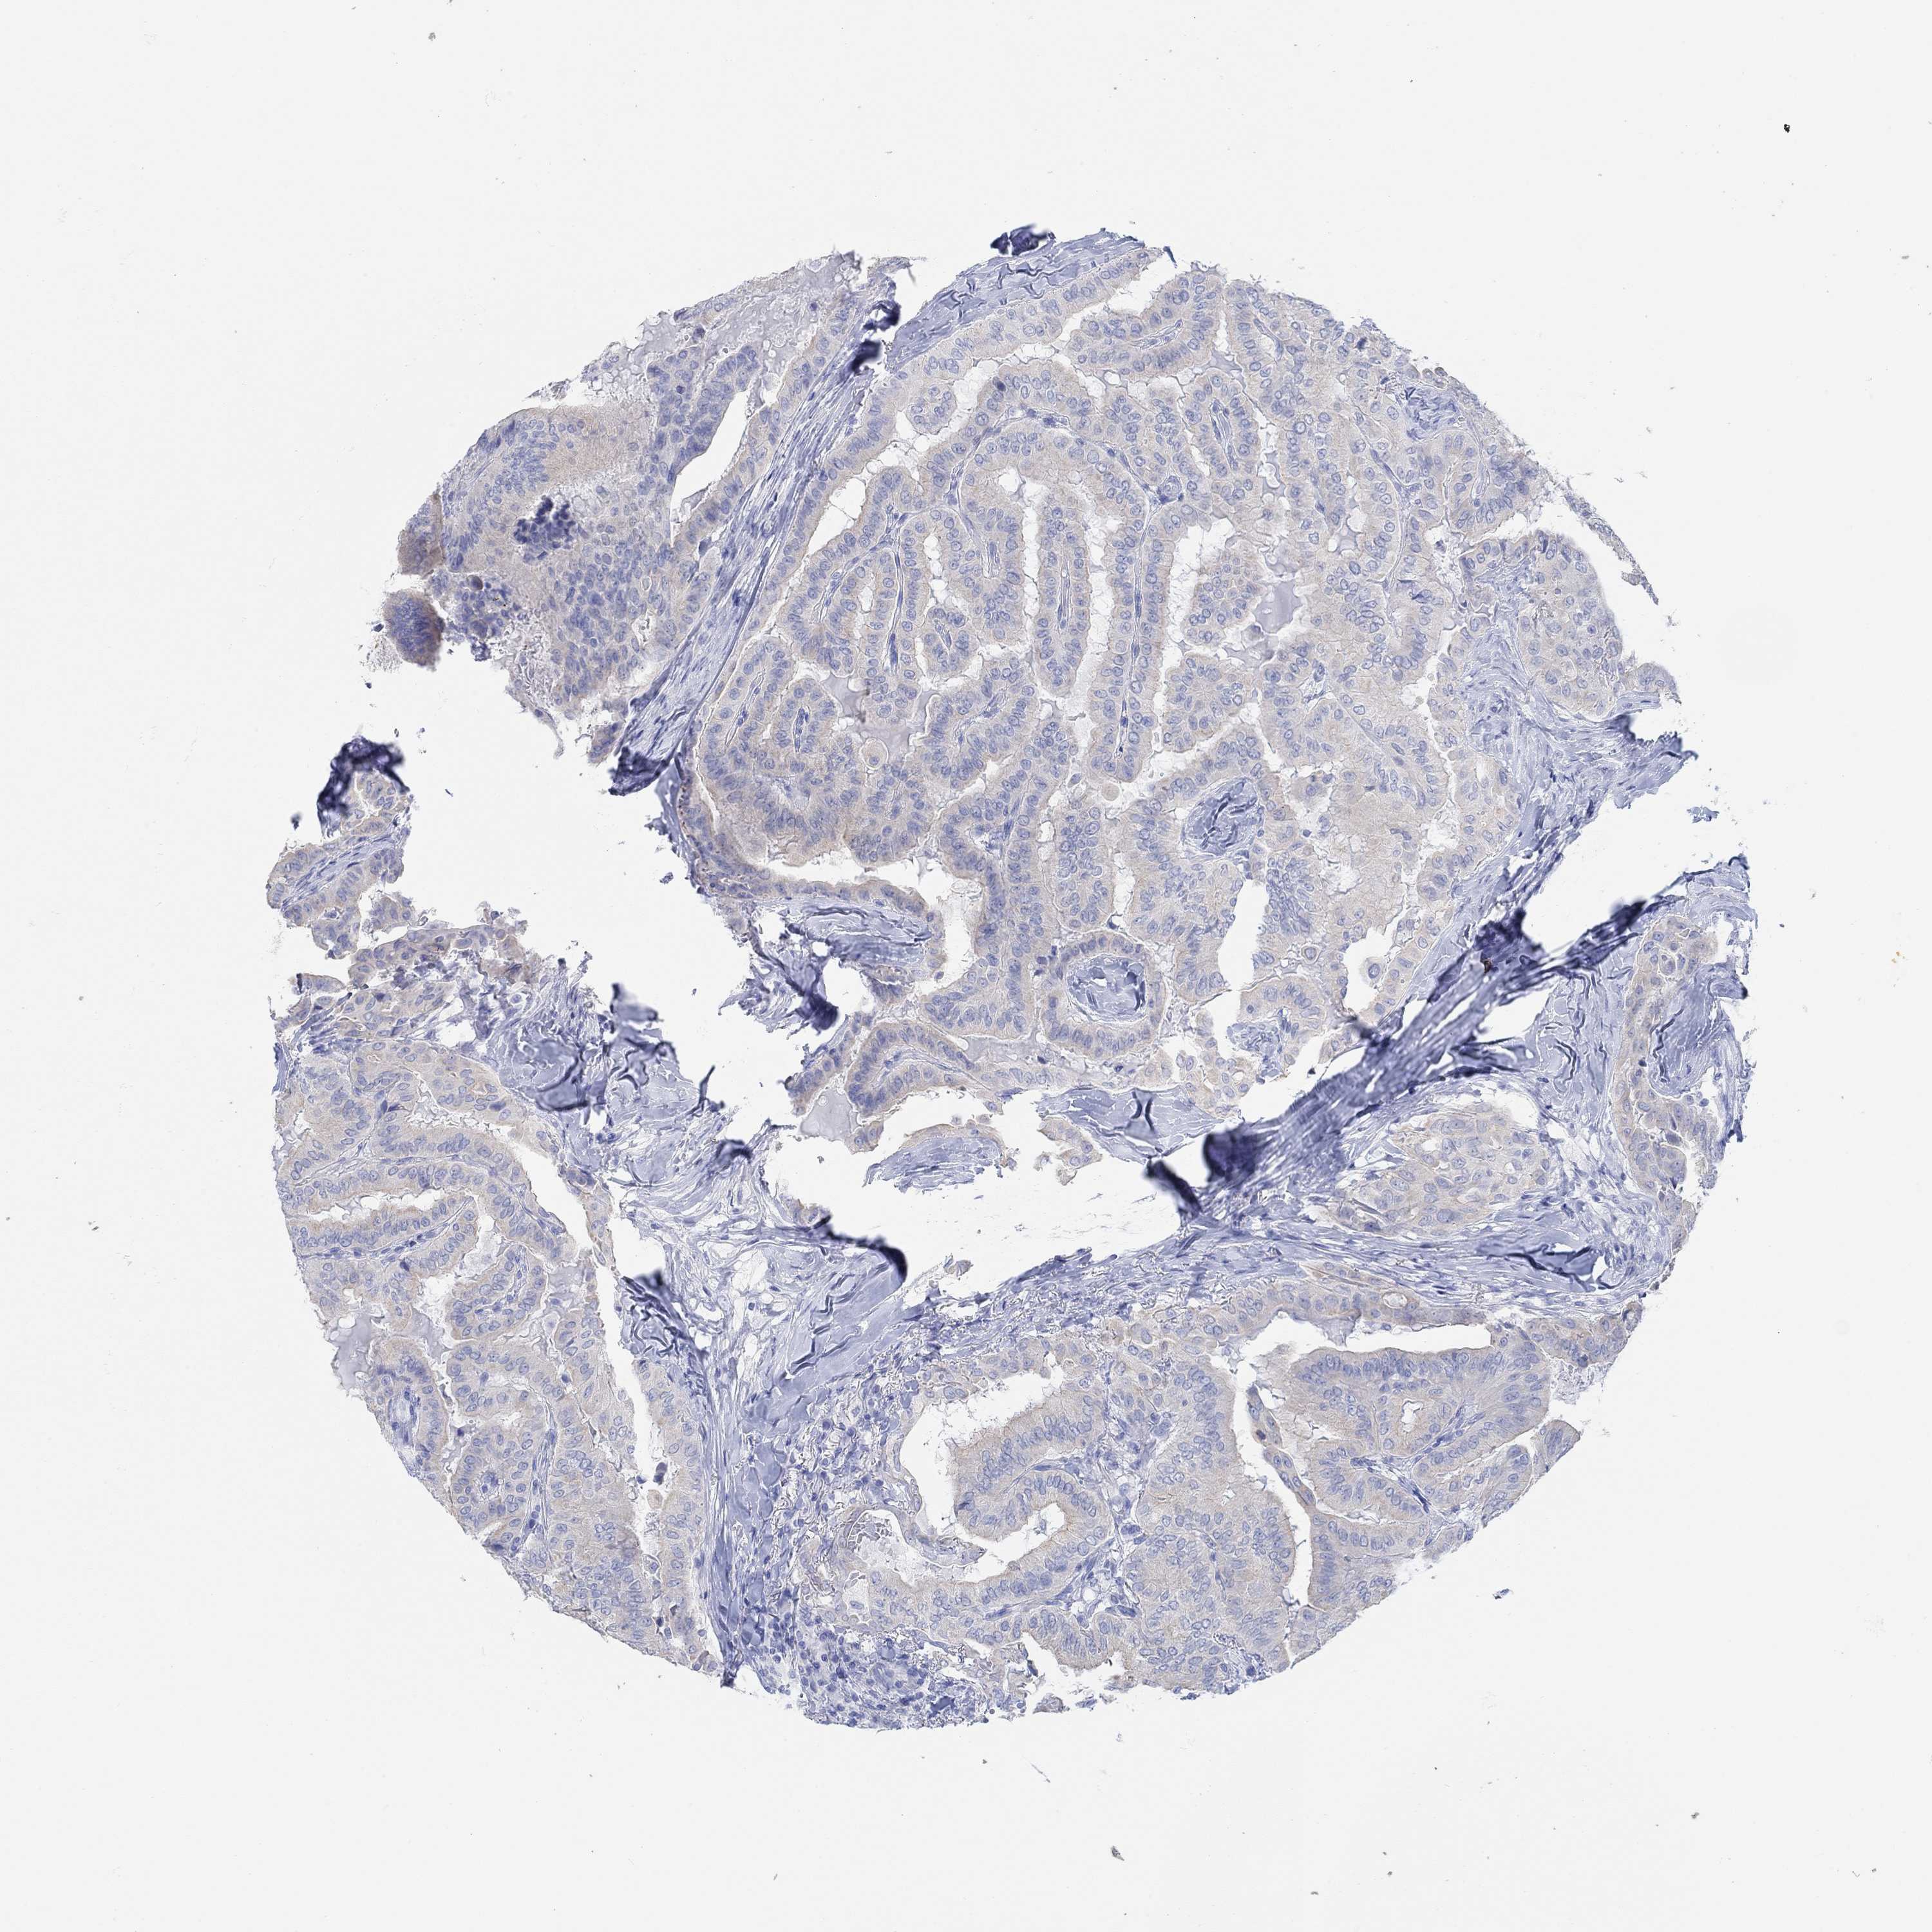

THYROID CANCER - Protein expressioni

A mouse-over function shows sample information and annotation data. Click on an image to view it in a full screen mode. Samples can be filtered based on level of antibody staining by selecting one or several of the following categories: high, medium, low and not detected. The assay and annotation is described here.

Note that samples used for immunohistochemistry by the Human Protein Atlas do not correspond to samples in the TCGA dataset.

Antibody stainingi

Antibody staining in the annotated cell types in the current human tissue is reported as not detected, low, medium, or high, based on conventional immunohistochemistry profiling in selected tissues. This score is based on the combination of the staining intensity and fraction of stained cells.

Each image is clickable and will lead to virtual microscopy that enables deeper exploration of all samples and also displays staining intensity scores, fraction scores and subcellular localization as well as patient and tissue information for each sample.

Antibody HPA021443

Antibody HPA023894

Staining

High

Medium

Low

Not detected

Intensity

Strong

Moderate

Weak

Negative

Quantity

>75%

75%-25%

<25%

None

Location

Nuclear

Cytoplasmic/membranous

Cytoplasmic/membranous,nuclear

Papillary adenocarcinoma, NOS

Follicular adenoma carcinoma, NOS